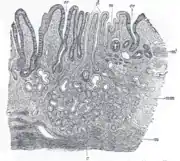

The GI tract is essentially a hollow tube connecting the mouth to the anus. The GI tract has a similar layout through out its length:

- An inner mucosal layer with an epithelial lining

- A submucosal layer

- A thin layer of muscle , the Muscularis Mucosa is at the junction of the mucosal and sub mucosal layers, outside this are the nerves of the mucosal plexus

- A muscular layer with an inner circular muscle layer and an outer longitudinal layer

- Between the muscles are the nerves of the myenteric plexus

- A serosal layer which is continuous with the mesentry

This is illustrated graphically here: